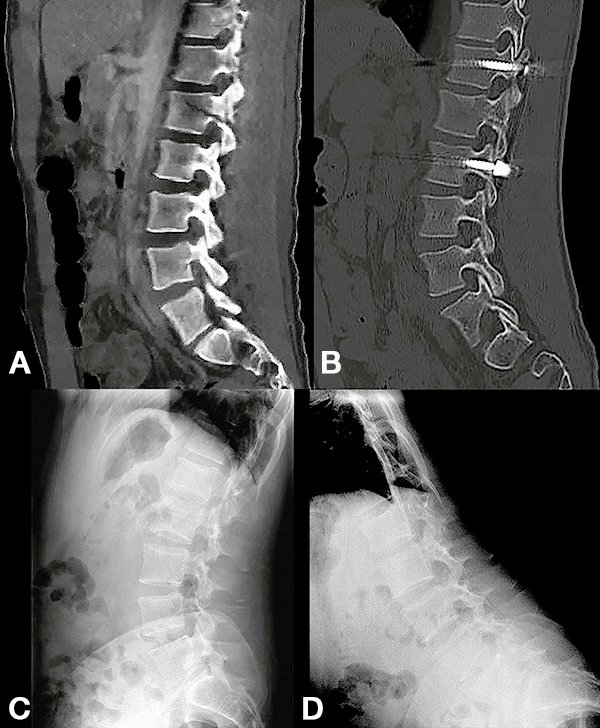

Caso 24. A: Fractura L1: B1; N1. B: Control 7 meses que evidencia consolidación. C y D: Retiro de osteosíntesis a los 9 meses con buena movilidad en las radiografías dinámicas de control.

Figura 6:

Caso 8. A la semana de la primer cirugía el paciente se encontraba en condiciones y se realizó la corpectomía por via lateral MIS.

Figura 7:

Caso 8. Control postoperatorio alejado del paciente con un buen callo de fusión, sin pérdida de corrección.